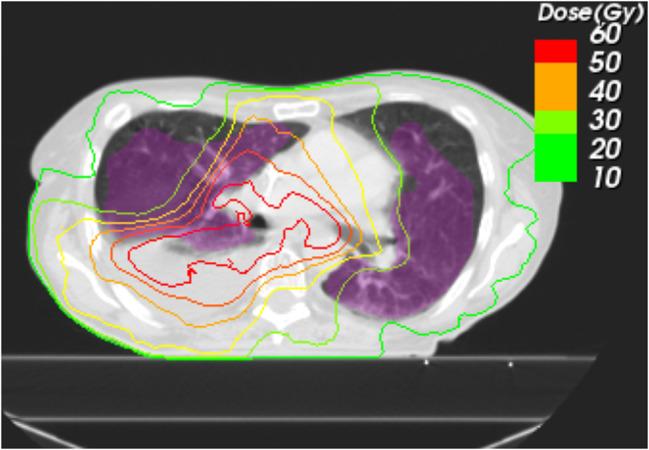

PTP volumes were delineated on the follow-up diagnostic Computed Tomography (CT) and deformably matched to the planning CT for patients with PTP after thoracic R(C)T + ICI or R(C)T. Dose data was converted to 2-Gy equivalent doses (EQD2) and dosimetrically analyzed. Dosimetric and volumetric parameters of the segmented PTP volumes were analyzed. The method was exemplarily tested on an internal patient cohort including 90 patients having received thoracic R(C)T + ICI (39) and R(C)T (51). Thirtytwo patients with PTP were identified for further analysis. Additional data on previous chemotherapy, RT, smoking status and pulmonary co-morbidity were conducted. A matched pair analysis with regard to planning target volumes (PTV) was conducted for curative intended (definitive) and palliative patient cohorts individually.

The presented method was able to quantify and compare the dosimetric parameters of PTP for the different therapies. For our study group, no significant differences between R(C)T + ICI and R(C)T only was observed. However, the dosimetric analysis revealed large volumetric fractions (55%) of the PTP volumes to be located outside of high dose (EQD2 < 40 Gy) regions for R(C)T + ICI. There was a non-significant trend towards increased area under the curve of the dose volume histogram (AUC) values for R(C)T + ICI compared to R(C)T only (3743.6 Gy∙% vs. 2848.8 Gy∙%; p-value = 0.171). In contrast to the data for the palliative intended treatment group, for definitive R(C)T + ICI, data tended towards increased volumes with higher doses.